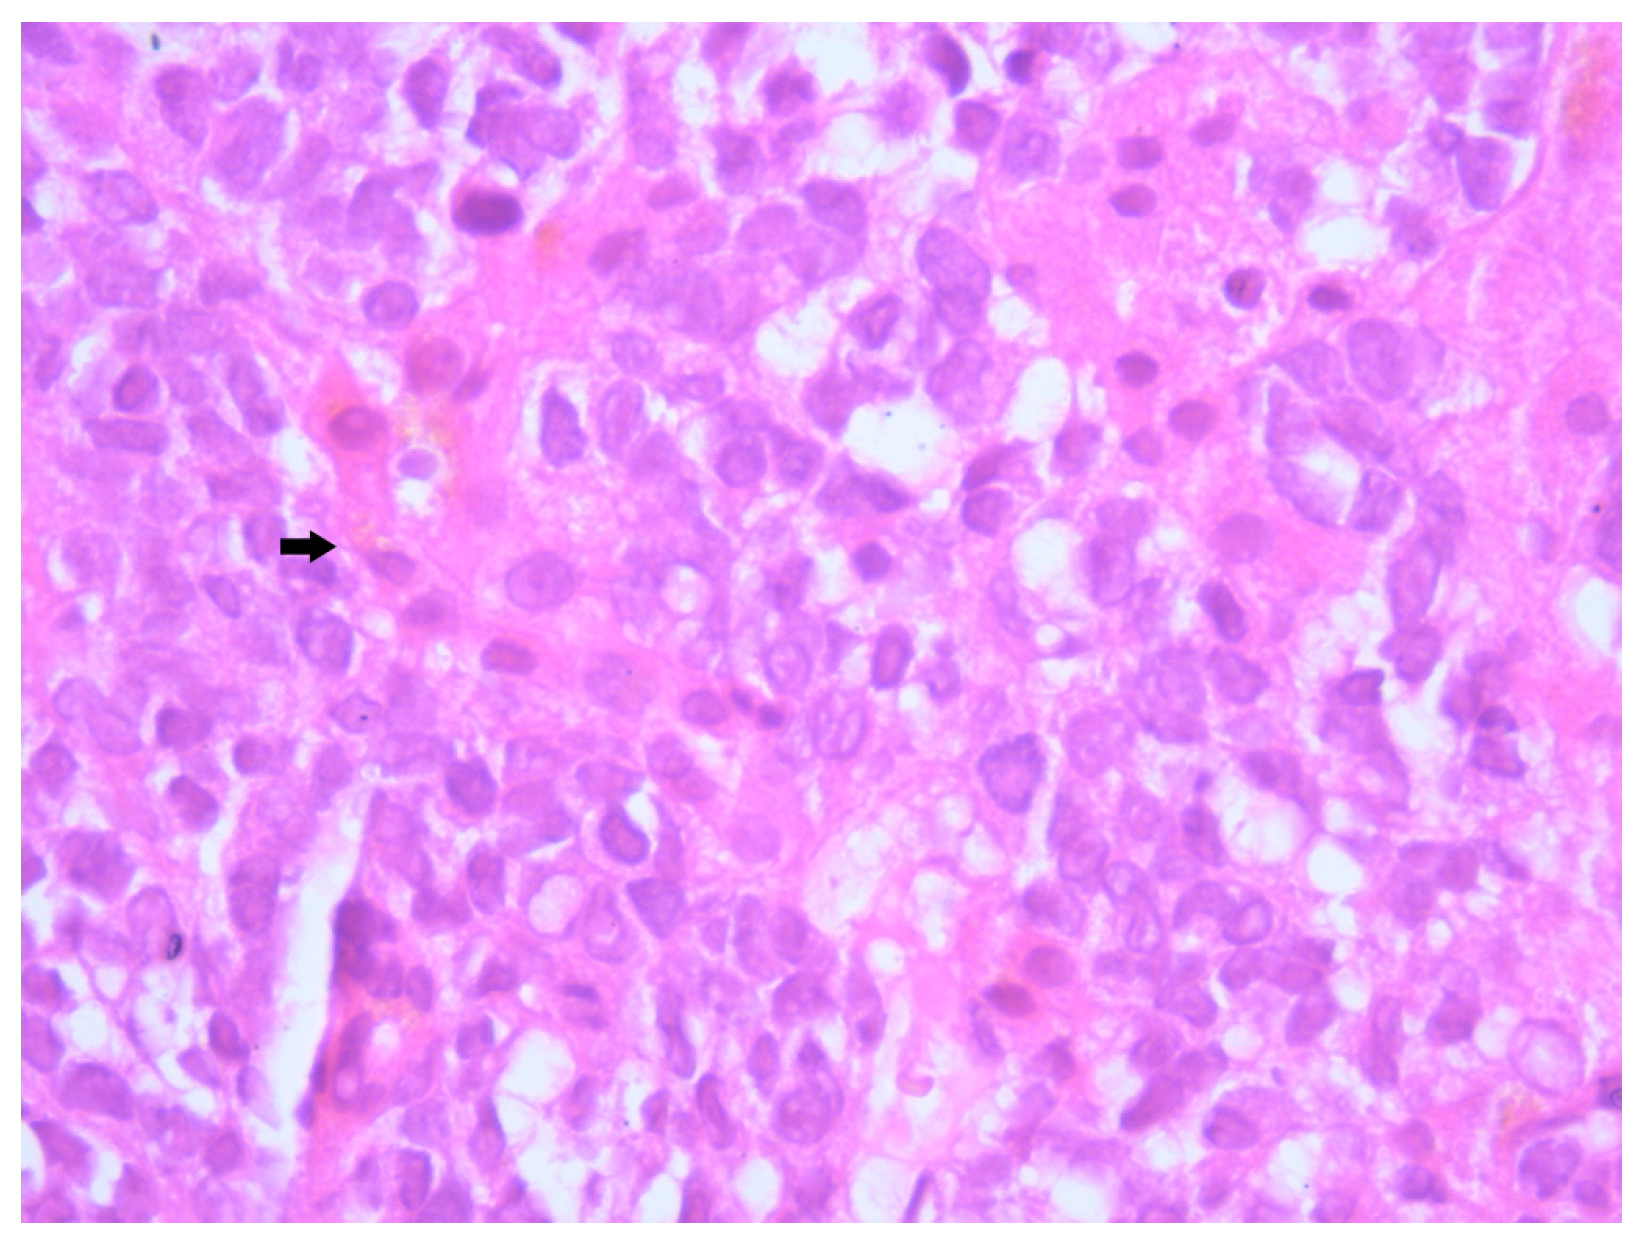

Figure 5. Hematoxylin–Eosin staining, 10× magnification (HE 10×): Tumoral proliferation composed of diffusely arranged cells forming sheets of variable sizes, separated by minimal stroma. Arrows highlight clusters of small round blue cells arranged in diffuse sheets.

Histopathological examination of the liver biopsy revealed fragments of hepatic parenchyma measuring 10 × 1 mm, with tumoral infiltration by small, round blue cells exhibiting indistinct cytoplasmic borders, scant eosinophilic cytoplasm and round to oval nuclei that were either hyperchromatic or euchromatic, with finely granular chromatin and absent nucleoli. Occasional mitotic figures (4 per 3 HPFs) were identified. The morphology was consistent with a small round blue cell tumor, raising differential diagnostic considerations (Figure 4, Figure 5 and Figure 6). Small round blue cell tumors involving the liver include lymphoma, plasmacytoma, metastatic small-cell lung carcinoma, high-grade neuroendocrine carcinoma, metastatic melanoma, metastatic neuroblastoma and Ewing sarcoma. In contrast to these entities, MCC usually presents with a rapidly growing cutaneous primary tumor, satellite or in-transit metastases and early involvement of regional lymph nodes, as seen in our patient. The combination of morphology (small round blue cells with scant cytoplasm and neuroendocrine features), the presence of a violaceous primary lesion on a sun-exposed site, satellite nodules, marked axillary lymphadenopathy and rapid multiorgan dissemination made MCC the most consistent diagnosis, despite the absence of immunohistochemistry. To clarify the cellular origin and reach a definitive diagnosis, correlation with clinical and paraclinical data, along with immunohistochemical testing (e.g., CK AE1/AE3, CK20, CD56, Chromogranin A, SOX10, CD20, CD3, CD138), would have been essential. The liver biopsy was obtained while the patient was hemodynamically unstable, and within hours he developed biopsy-related hemoperitoneum, shock and multiorgan failure, requiring transfer to the ICU. Due to the rapid clinical deterioration and death shortly afterward, the sample could not be processed for IHC in time, and further invasive tissue sampling was no longer ethically indicated. Nevertheless, the combination of clinical presentation (violaceous cutaneous tumor with satellite nodules), imaging (multiorgan metastases) and morphology of the liver sample (small round blue cells with neuroendocrine features) supported the presumptive diagnosis of metastatic MCC. According to the 8th edition of the American Joint Committee on Cancer (AJCC) staging system for MCC, this case corresponds to Stage IV—cT2N3M1c disease. The T2 classification applies because the primary cutaneous tumor was >2 cm. N3 reflects the presence of clinically evident, macroscopic lymph node involvement together with in-transit metastases (satellite cutaneous nodules). The M1c designation is supported by multiple visceral metastases involving the liver, spleen and suspected bone lesions on CT imaging.

MCC classically exhibits morphological features including small round cells with scant cytoplasm, nuclear molding, and hyperchromatic nuclei with finely granular “salt and pepper” chromatin—features reflective of its neuroendocrine differentiation [13]. In our patient, microscopic examination revealed a proliferation of small, undifferentiated cells with high nuclear-to-cytoplasmic ratio, frequent mitotic figures and dense nuclear chromatin, consistent with these hallmarks. Unfortunately, due to the fulminant clinical deterioration and subsequent death of the patient, immunohistochemical (IHC) profiling could not be completed. Nevertheless, the suggestive histological pattern in combination with the rapid evolution and metastatic behavior strongly supported the diagnosis of MCC. While IHC remains critical for definitive diagnosis, particularly to differentiate MCC from other small round blue cell neoplasms, the clinicopathological context provided sufficient grounds for a diagnosis.